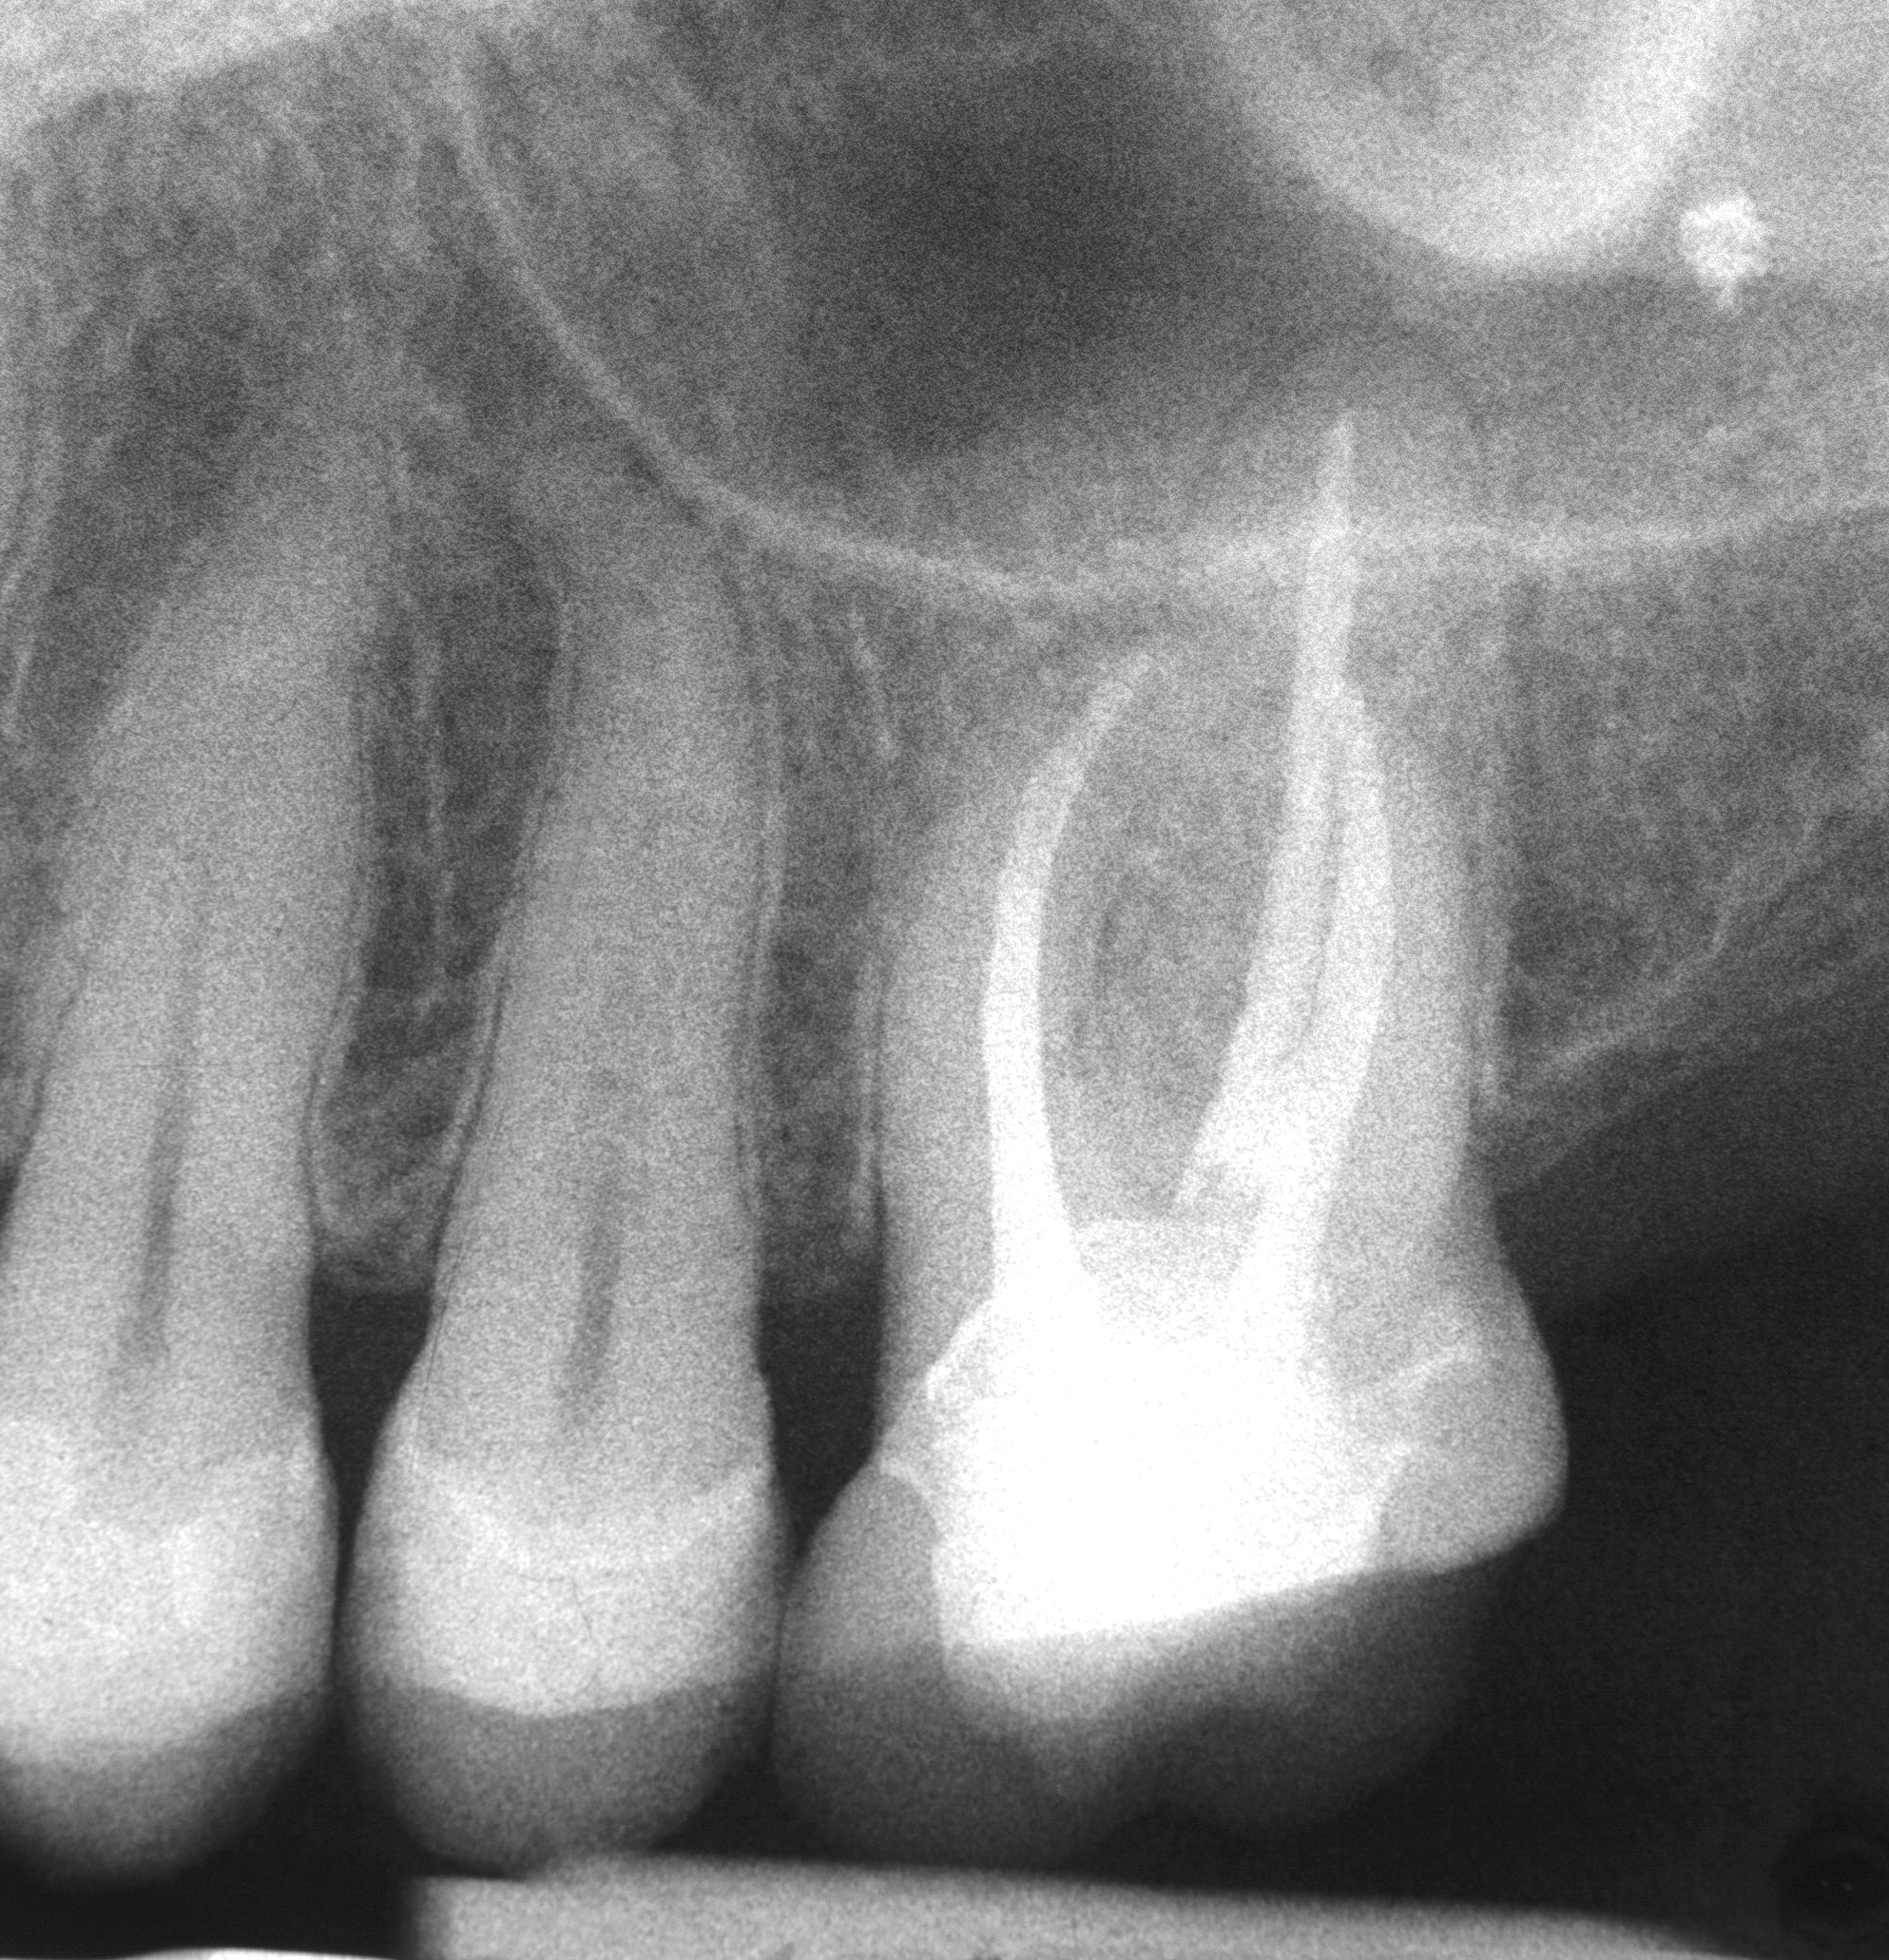

Druckfähiges Bildmaterial zum Download: